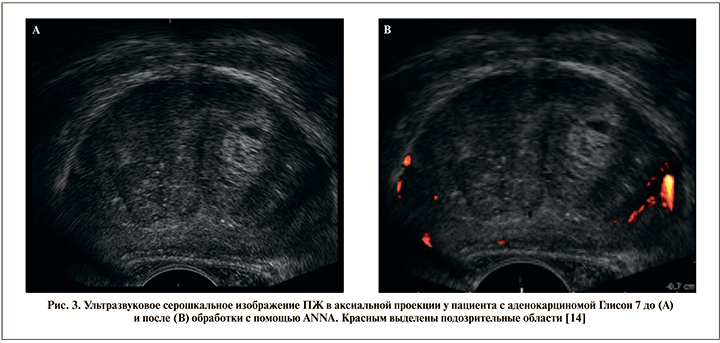

Для улучшения результативности серошкального УЗИ для выявления РПЖ разработано несколько компьютерных программ, анализирующих полученные УЗ-изображения. Лучшие результаты принадлежат нейронной сети, оценивающей с помощью специального алгоритма статические ТРУЗ-изображения ПЖ (artificial neuronal network analysis, ANNA-TRUS). Врач, выполняющий биопсию, по защищенному каналу пересылает УЗ-данные исследования на специальный сервер. Нейронная сеть оценивает полученный визуальный ряд и маркирует подозрительные области ПЖ, затем отсылает данные обратно врачу для выполнения таргетной биопсии (рис. 3).